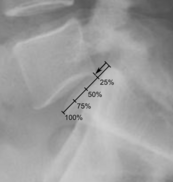

Степень соскальзывания

Боковая рентгенограмма покажет степень смещения позвонка к нижележащему:

• Степень I — смещение до 25 %.

• Степень II — смещение от 26 % до 50 %.

• Степень III — смещение от 51 % до 75 %.

• Степень IV — смещение от 76 % до 100 %.

• Степень V развивается, когда позвонок полностью отделяется от соседнего позвонка (спондилоптоз).